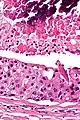

Their histologic appearance is similar to ductal breast carcinoma.